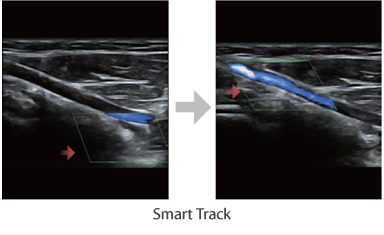

Многофункциональная система DC-60 Exp с X-Insight представляет собой комплексное решение, которое помогает управлять повседневной клинической практикой с легкостью и уверенностью.

Основываясь на глубоком понимании потребностей клиентов, компания Mindray разработала систему DC-60 Exp с X-Insight, чтобы обеспечить высокую производительность и точность визуализации вкупе с наглядностью, исключительной интеллектуальностью и огромным опытом.